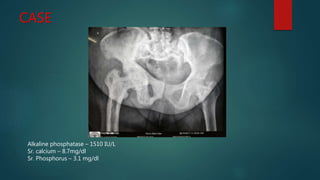

CASE

Alkaline phosphatase – 1510 IU/L

Sr. calcium – 8.7mg/dl

Sr. Phosphorus – 3.1 mg/dl

CASE Alkaline phosphatase –1510 IU/L Sr. calcium – 8.7mg/dl Sr. Phosphorus – 3.1 mg/dl